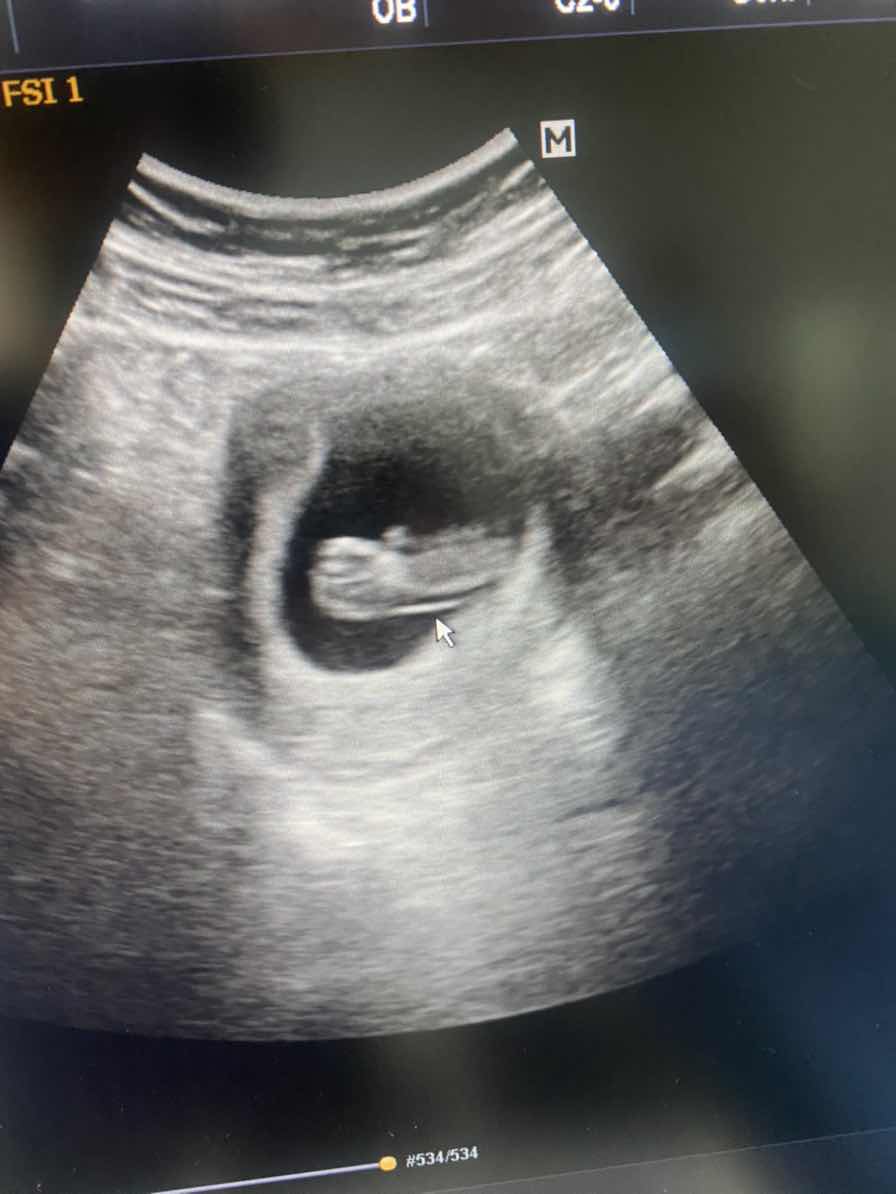

3 ธันวา ซาวด์ตอน9วีคค่ะ

3 ธันวา ค่าา ซาวส์ตอน 9w